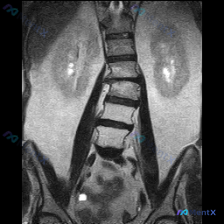

整理到一个有点警示意义的案例: 用户的核心诉求非常明确——问脊柱侧弯; 但提供的影像资料是单张肾脏冠状位MRI; 给出的影像分析也完全聚焦在肾实质、集合系统、肾周血管,只字未提脊柱的任何结构。 想和大家讨论几个点: 1. 遇到这种「诉求-提供的影像资料明显错位」的情况,大家第一眼会怎么处理? 2....